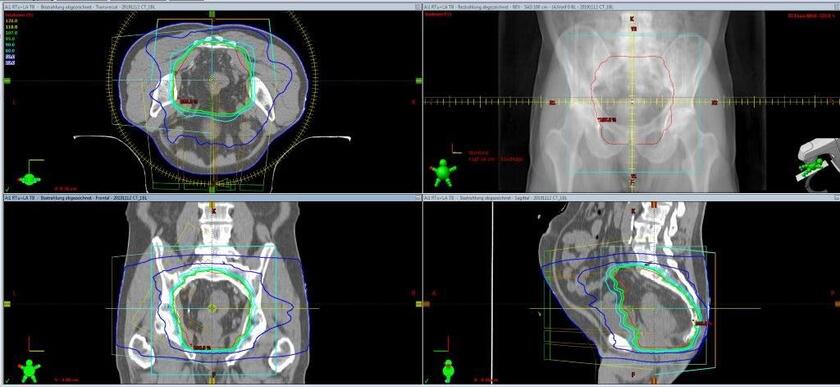

Bestrahlungsplan in Bauchlage für einen Patienten mit Enddarmkrebs.

Bei Patienten mit Enddarmkrebs (Rektumkarzinom) führen wir die Bestrahlung in Rückenlage oder in Bauchlage durch. Das heißt, für den Patienten wird ein Bestrahlungsplan für beide Lagerungen erstellt. Anschließend wird mit dem Behandlungsplan bestrahlt, mit dem eine bessere Schonung von Harnblase und Dünndarm gewährleistet werden kann.